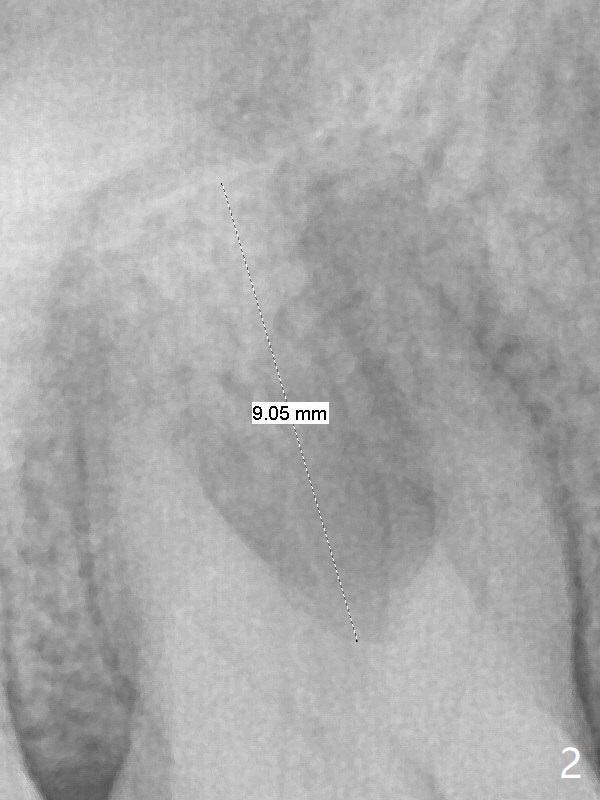

A 53-year-old woman has crack tooth symptom at #3 with apparently a vertical crack line on PA (Fig.1 arrow), suggesting bruxism. The latter may be easily associated with abutment screw loosening. To avoid this complication, a tissue-level implant will be placed (Fig.3). After extraction, the initial depth of osteotomy in the septum will be 7 mm (Fig.2). Find a pointed drill. Take preop photos to show the possible buccal crack line.